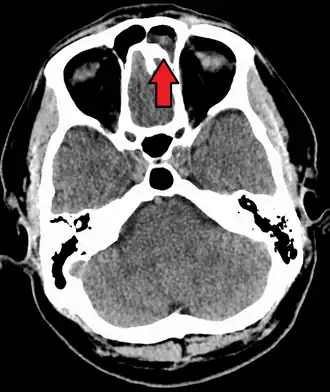

MRI image showing sinusitis. Edema and mucosal thickening appear in both maxillary sinuses. -

Frontal sinusitis -